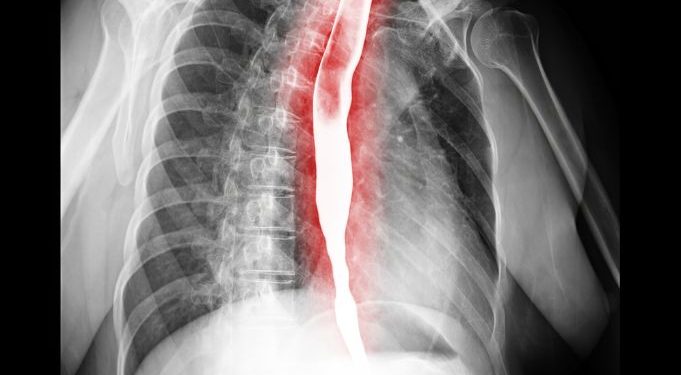

Some of the most common symptoms of esophageal atresia and tracheoesophageal malformations are a dry, coughing, or a coughing that sounds like a baby is sick. It is important to see a doctor right away if you notice these signs. X-rays can be taken to check for esophageal atresia. The doctor can also perform a rigid bronchoscopy to view the baby’s windpipe.